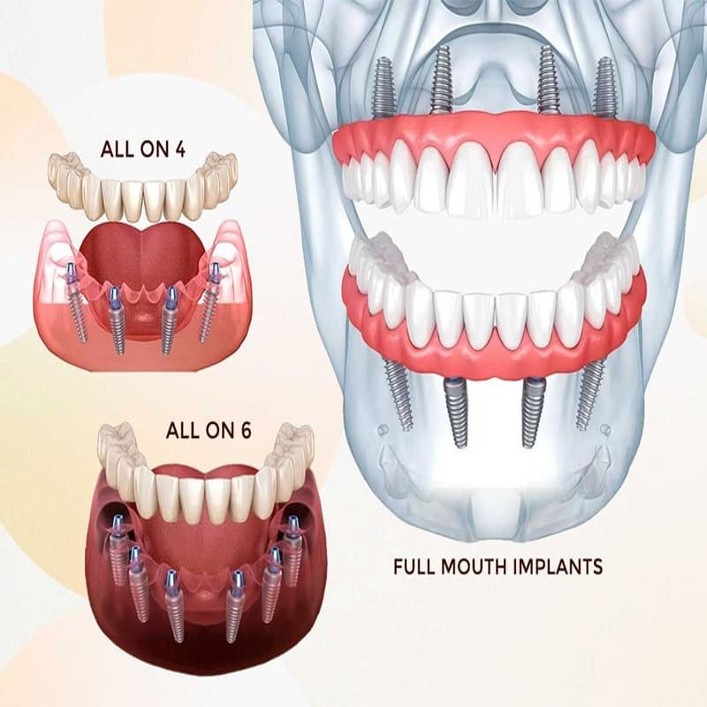

A comprehensive dental treatment designed to restore the function, health, and appearance of the teeth,involving proceduers like crowns, bridges, implants, and veneers to fix issues like severe wear, missing teeth, bite problems or truma essentially rebuilding your enteir bite and smile.